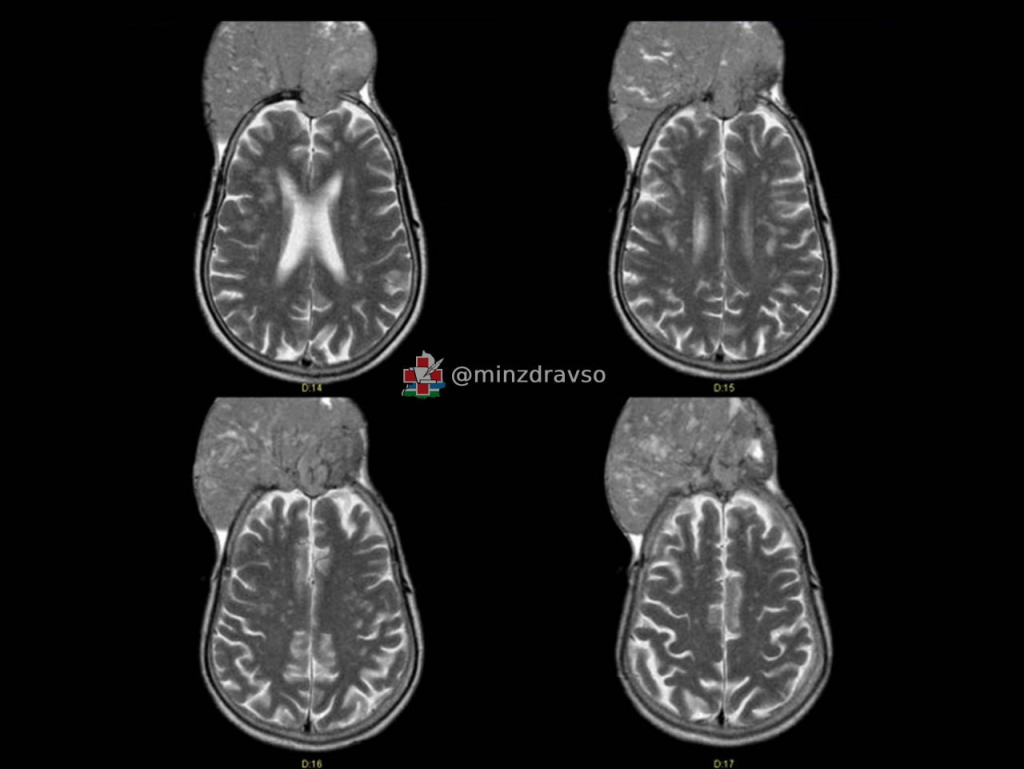

Хирурги из Свердловского областного онкологического диспансера спасли жителя краснотурьинца, у которого опухоль мозга буквально проросла через череп.

Как рассказали на информационном ресурсе «Здоровье уральцев» министерства здравоохранения региона, у мужчины была менингиома – одна из самых распространённых опухолей. Она доброкачественная, но может вызывать нарушения слуха, зрения, речи, чувствительности, двигательной активности, и без своевременной терапии создавать угрозу для жизни.

Этот пациент поступил в отделение нейроонкологии, когда опухоль «съела» кости черепа и выросла наружу на 10 сантиметров.

Фото: министерство здравоохранения Свердловской области